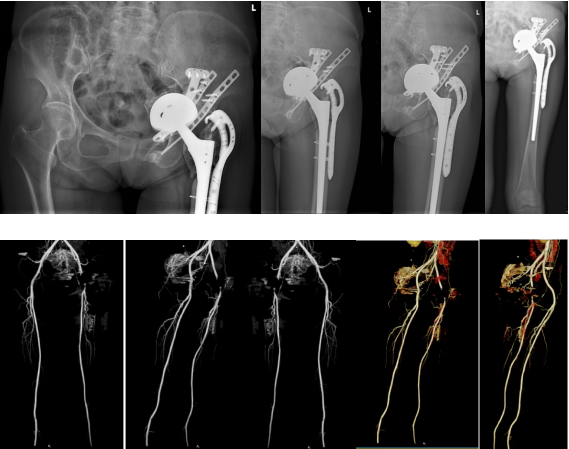

为求进一步诊治,患者于术后1年(今年6月)来到华西医院,找到关节外科康鹏德教授。经过检查,提示患者左髋臼假体松动,伴髋臼大量骨缺损,已形成慢性骨盆不连续的状态。假体突破髋臼内壁向内上方移位接近中线,突入盆腔内部,并靠近盆腔内脏器官如子宫、膀胱、直肠等以及盆腔内重要血管。髋关节是人体内最大的承重关节,现患者髋臼假体突入盆腔,髋关节自然不能完成其生理功能,因此患者无法正常站立行走。

同时,该患者的股骨转子间存在骨折,术后1年骨折线仍然存在,提示该处骨折不愈合。患者的盆腔CT血管造影,提示左侧髂动脉与突入盆腔内的髋臼假体关系密切,髂血管被突入盆腔的髋臼假体压迫并粘连,这意味着在假体取出的过程中有可能损伤盆腔动脉,引发术中大出血。

图 术前患者骨盆片以及血管CTA